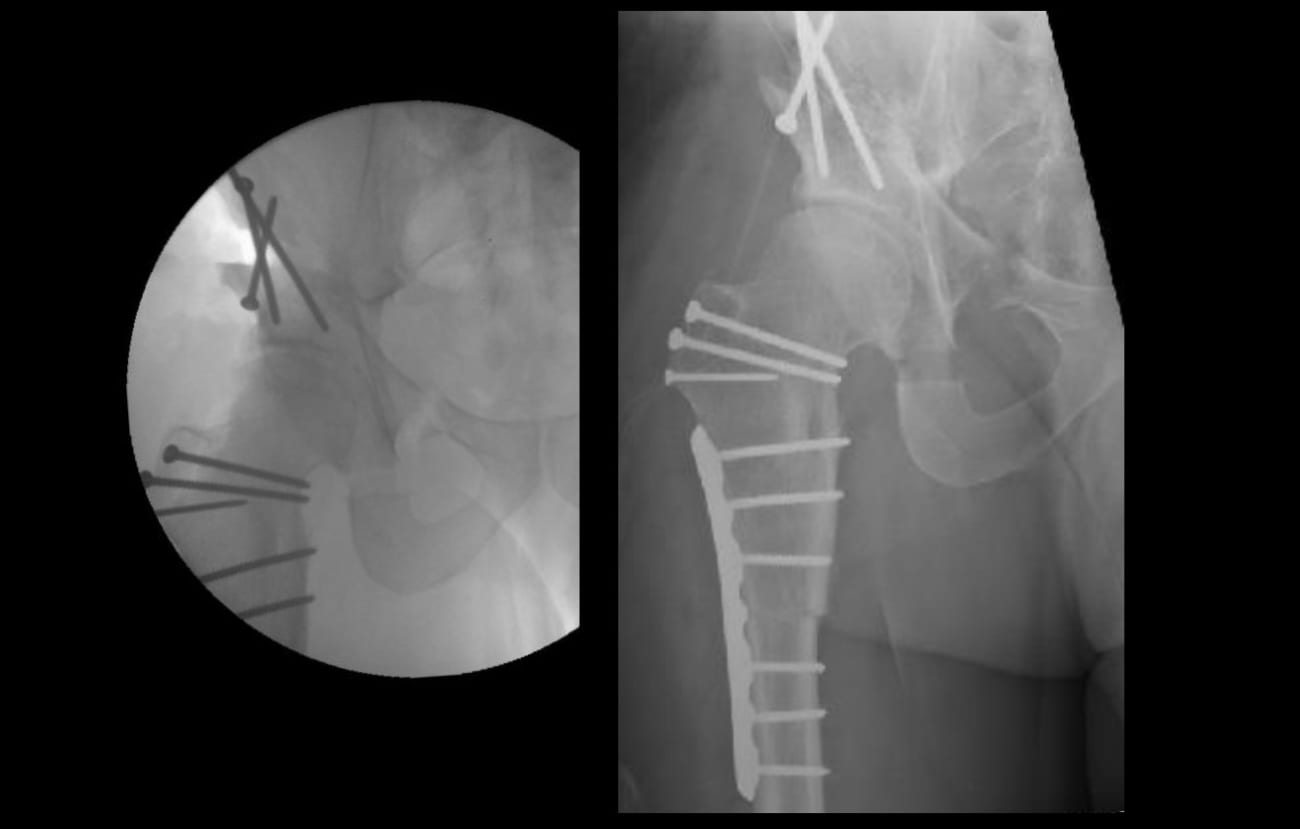

Although Mr. J’s intra-articular causes of FAI were optimized, the extra-articular rotational deformity of the femur did not allow for adequate impingement-free range of motion. Therefore, a subtrochanteric derotational osteotomy with internal fixation was performed to bring the femur into normal rotational alignment. Bone autograft harvested from the greater trochanteric bed was used to supplement the osteotomy fixation (Fig. 2).